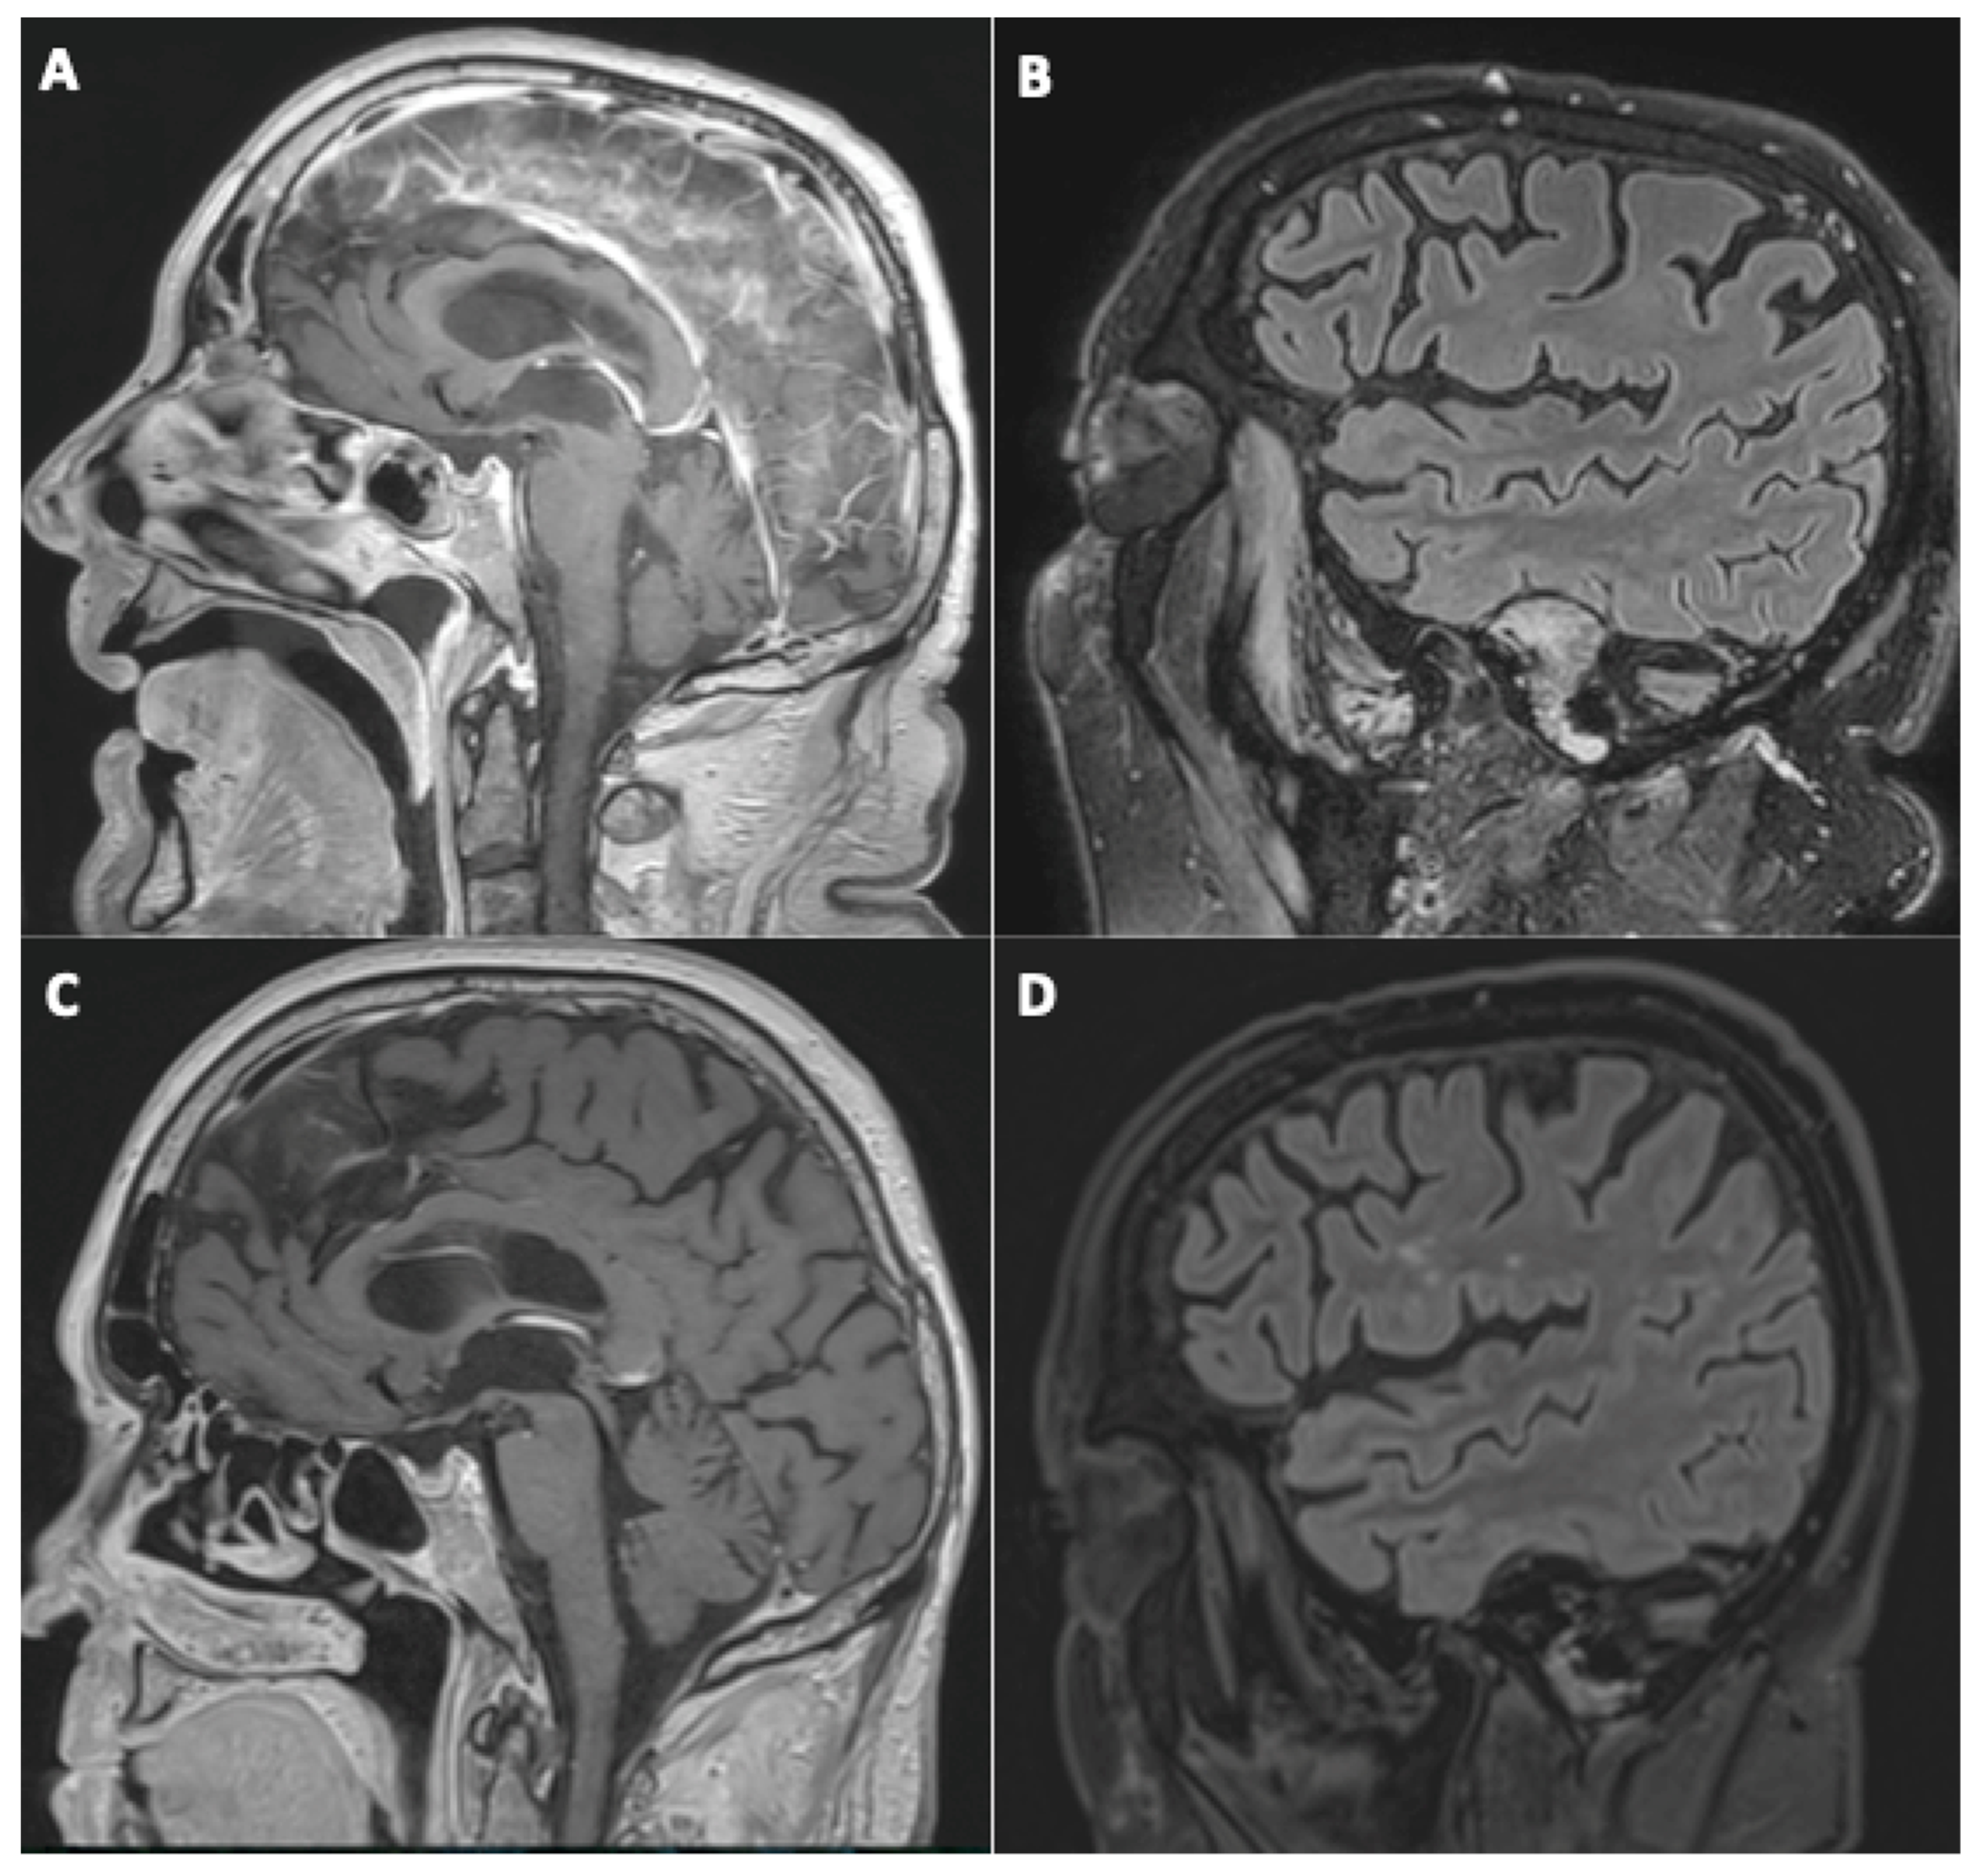

3.1. Brain MRI Findings

- Initial brain MRI findings

- Fourteen (45%) cases of focal (single focus or multiple foci) leptomeningeal enhancement (LME);

- Nine (29%) diffuse brain microhemorrhages, which predominantly involved the corpus callosum, the subtentorial juxtacortical WM, the internal capsule, the brainstem, the middle cerebellar peduncles, and the cerebellum, leading to the diagnosis of critical-illness associated cerebral microbleeds (CIAM) [14];

- Four (13%) acute ischemic strokes (acute small vessel infarcts or borderline infarction);

- Evolution of initial neuroimaging findings

- New findings during follow-up

- Evolution of perfusion imaging